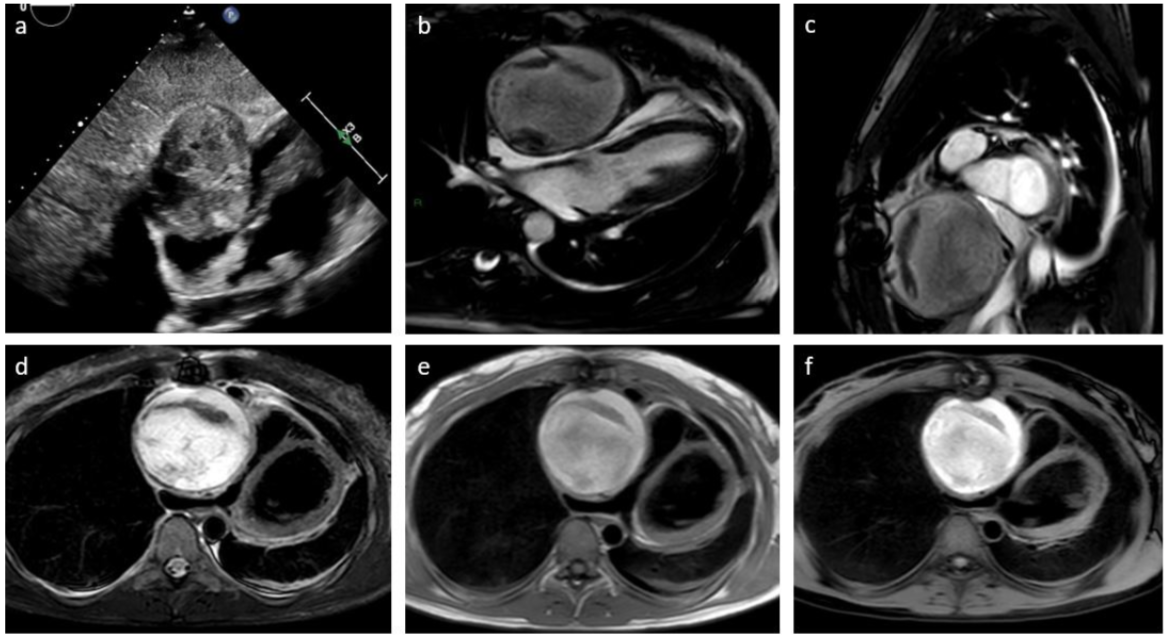

Sequence | Plane / Coverage | Slice Thickness |

b-SSFP cine | 2-chamber, 4-chamber and short-axis views | 8 mm |

Axial T1W-BB | Transaxial, whole thorax | 5 mm |

Axial T1W-BB FS | Transaxial, whole thorax | 5 mm |

T2W-STIR | Best plane for mass study (usually short-axis view) | 5 mm |

Native T1 Mapping (MOLLI) | Short-axis view | 10mm (1-2 slices including the mass) |

T2 Mapping (mGraSE) | Short-axis view | 10mm (1-2 slices including the mass) |

First-pass perfusion (rest) | 3 short-axis slices + 1 2-chamber and 4 chamber slice | 10 mm |

EGE | Best plane for mass study (TI 500-550 ms; 2 min after contrast injection) | 5 mm |

FSPGR-3D T1W post-contrast | Whole heart | 2 mm |

LGE | 2-chamber, 4-chamber and short-axis views | 8 mm |

T1 Mapping enhanced (MOLLI) | Short-axis view | 10mm (1-2 slices including the mass) |